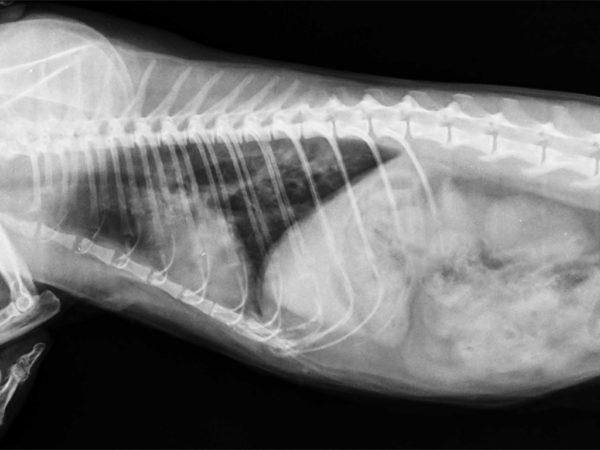

Если состояние вашего питомца стабильное, можно выполнить рентгенографию грудной клетки, положив собаку на спину. На этой рентгенограмме могут быть признаки отека легких, такие как повышенная интерстициальная или альвеолярная непрозрачность. У собак, страдающих кардиогенным отеком легких, также могут наблюдаться кардиомегалия и расширенные легочные вены.

Рентгеновские снимки являются основным инструментом для диагностики отека легких, поскольку они выявляют жидкость внутри легких собаки. Рентген также может выявить увеличенное сердце или другие аномалии сердечной мышцы.